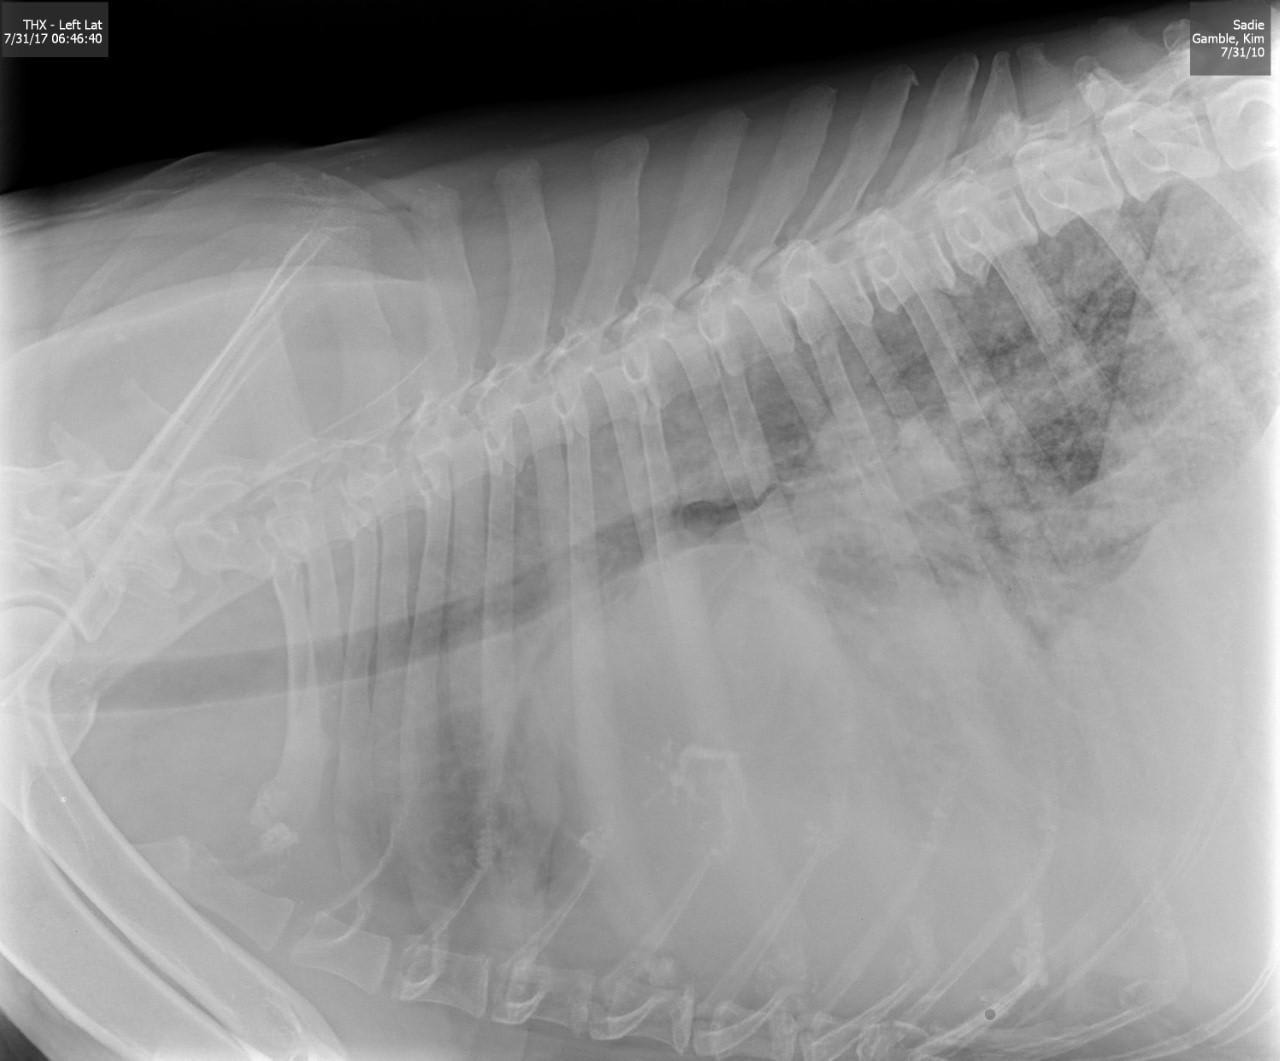

Pet's info: Dog | German Shepherd | Female | spayed | 7 years and 10 months old | 85 lbs

7 YR OLD GERMAN SHEPHARD, FLUID IN BELLY, HEAVY PAINTING, RAPID HEARTBEAT,STILL EATS, NO POOP, NO VOMIT, VET SAID SHES DYING SOON, BUT NO BLOODWORK WAS DONE AND GIVEN PREDNISOLONE & CLAVAMOX. HE SAID MAYBE CANCER, OR HEART, OR CIRVO SHES GETTING WORSE STILL HAVE NO ANSWER TO WHAT IS THE MATTER TO START TRYING TO HELP HER

Hi and thanks for using Petco Pet Education Center, formerly Petcoach! I'm so sorry to hear about Sadie. This sounds very serious. Anytime there is fluid in a body cavity, the situation is serious. I would need to know more to give a better answer but in a German Shepherd dog of this age, one thing is likely and that is a tumor of the spleen. These are called hemangioma or hemangiosarcoma or it could even be a hematoma or benign growth on the spleen that is bleeding. These are usually a surgical emergency especially if they are bleeding into the abdomen. Depending on what type of Other reasons for fluid to accumulate in the belly would be heart disease, liver disease, other tumors or masses in the abdomen, kidney problems. A tap of the abdomen (abdominocentesis) would reveal what the fluid is and maybe how to proceed. I would advise taking Sadie back to your vet or taking her somewhere else for a second opinion if you want to try to do something with her. And I would advise this as soon as you can get her there. Not sure if surgery is an option and that would depend on her condition and what you do comfortably afford for her. I'm so sorry again and I really hope that she gets better very soon.